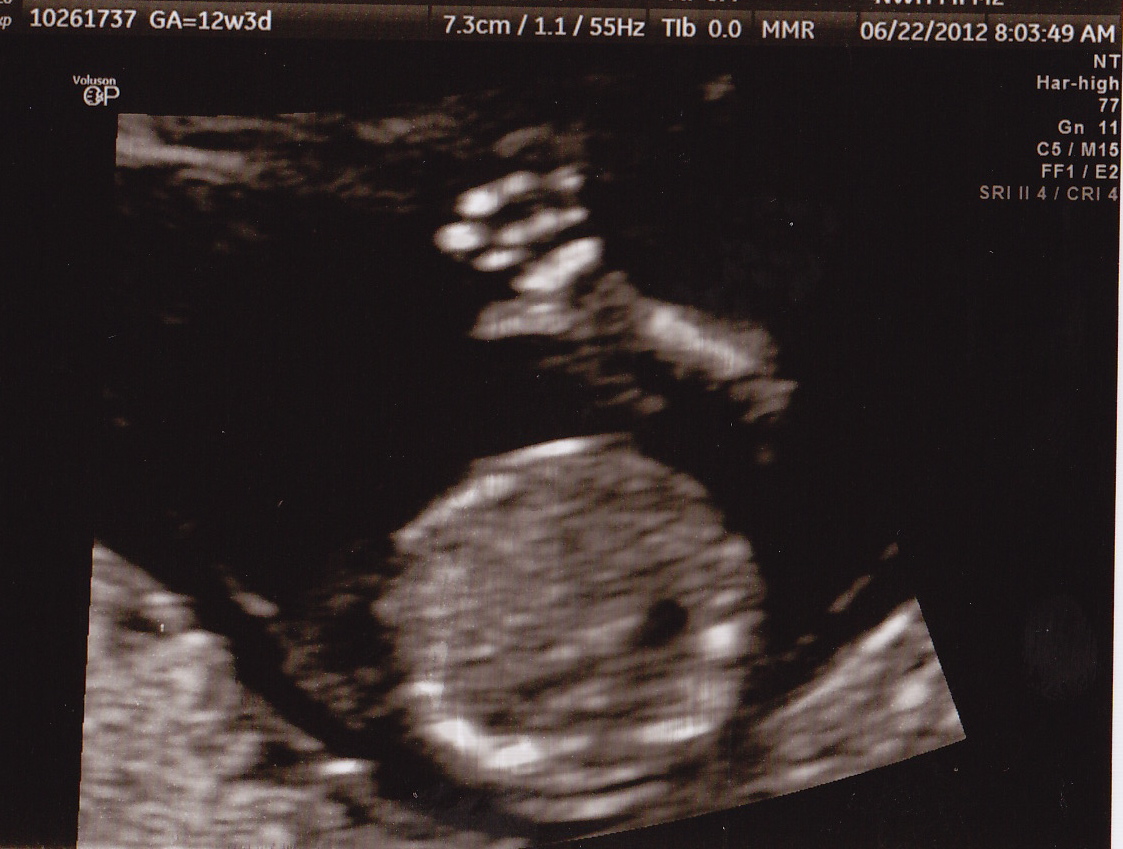

6/8/12 - First OB appointment at 10w3d. Heartbeat heard on doppler, 155 BPM.

5/30 - 9 weeks 1 day - Ultrasound #2 and release meeting with RE. Baby measured just right and 185 bpm.

| 5/14 - 7 weeks - Ultrasound #1: The Nugget is measuring right on track and had a heart rate of 130 bpm. |